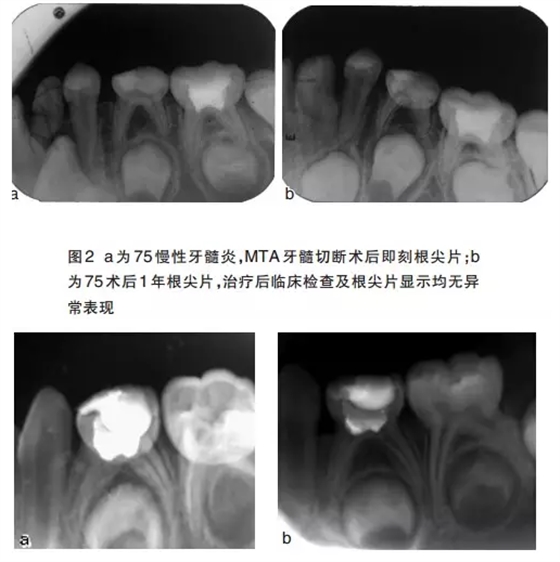

牙髓切斷術(shù)操作簡便,去除感染冠髓保留根髓活性,不刺激根尖周組織,使牙根繼續(xù)發(fā)育。但是牙髓切斷術(shù)后需要定期復(fù)查,通過臨床檢查和X線片判斷療效,經(jīng)常出現(xiàn)的失敗病例為牙齒的內(nèi)外吸收,在炎癥吸收的早期可行牙髓摘除術(shù)。如果臨床沒有癥狀,僅為X線片顯示的內(nèi)外吸收,也可以進行觀察,吸收嚴重時進行拔牙制作間隙保持器。MTA牙髓切斷術(shù)的患牙常常出現(xiàn)牙齒變色,因此不主張應(yīng)用于前牙。牙髓切斷術(shù)臨床使用見圖2~4。

適應(yīng)證 乳牙慢性牙髓炎,外傷露髓,齲齒去凈腐質(zhì)后露髓。

治療目標 剩余牙髓組織不發(fā)生進一步的感染或疼痛,腫脹。術(shù)后X線片沒有顯示牙根內(nèi)外吸收,牙根繼續(xù)發(fā)育,牙本質(zhì)橋形成。